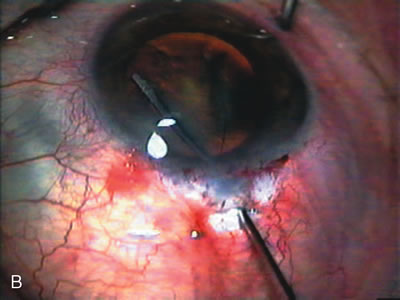

Fig. 7. Phacotrabeculectomy adjacent to a failed filter in cataractous eye. The ability to combine small-incision cataract extraction with trabeculectomy all through the same incision adjacent to the failed filter allows the surgeon to work in a familiar superior area. Avoiding incisions into the existing bleb decreases conjunctival buttonholes, hypotony, operating room time, and subconjunctival bleeding. A. Appearance of failed bleb with exposure of superior temporal quadrant gained with a corneal traction suture. B. Prepare a limbus-based conjunctival flap and a scleral flap. C. This bleb is at high risk to fail again justifying the need for MMC, 0.2 mg/cc applied on a pledget for 4 minutes. D. Insert the keratome and perform phacotrabeculectomy in the usual fashion.